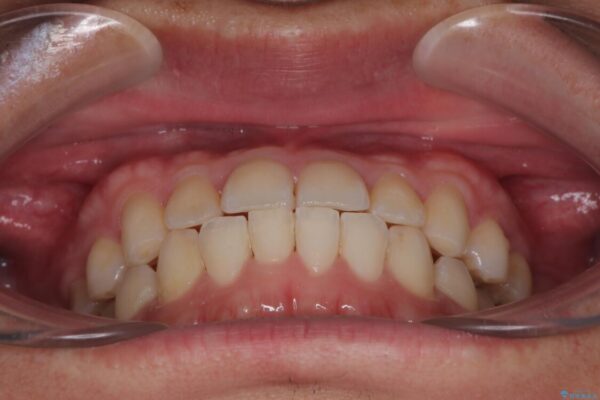

治療後

• 前歯のガタガタ・奥歯のかみ合わせ(シザーズバイト)を改善|1年半で完了したメタルブラケット矯正 治療後画像